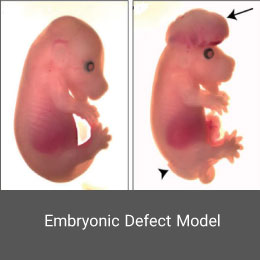

- Create and induce a variety of animal models